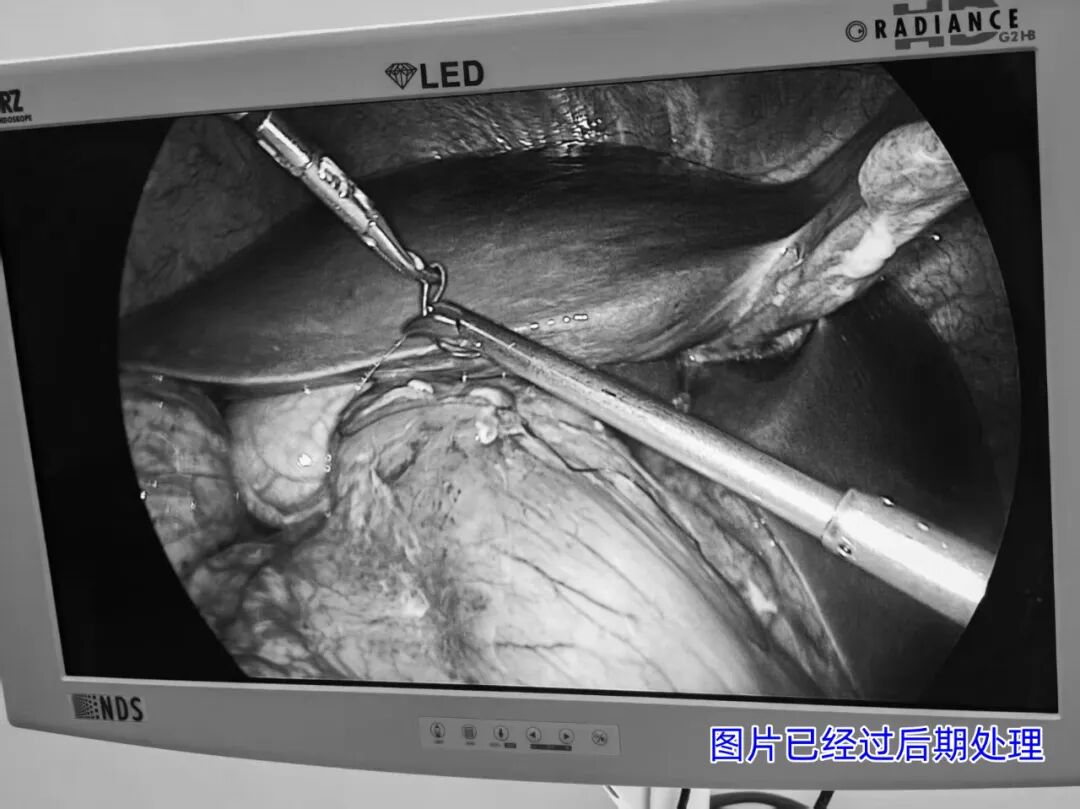

普外科团队迅速响应,根据患者情况制定了详细的手术方案。在手术室与麻醉科的密切配合下,由王兆太主任亲自带领普外科手术团队,为患者顺利实施了腹腔镜下胃溃疡穿孔修补术。手术过程顺利,患者术后恢复良好,目前已在进一步康复中。